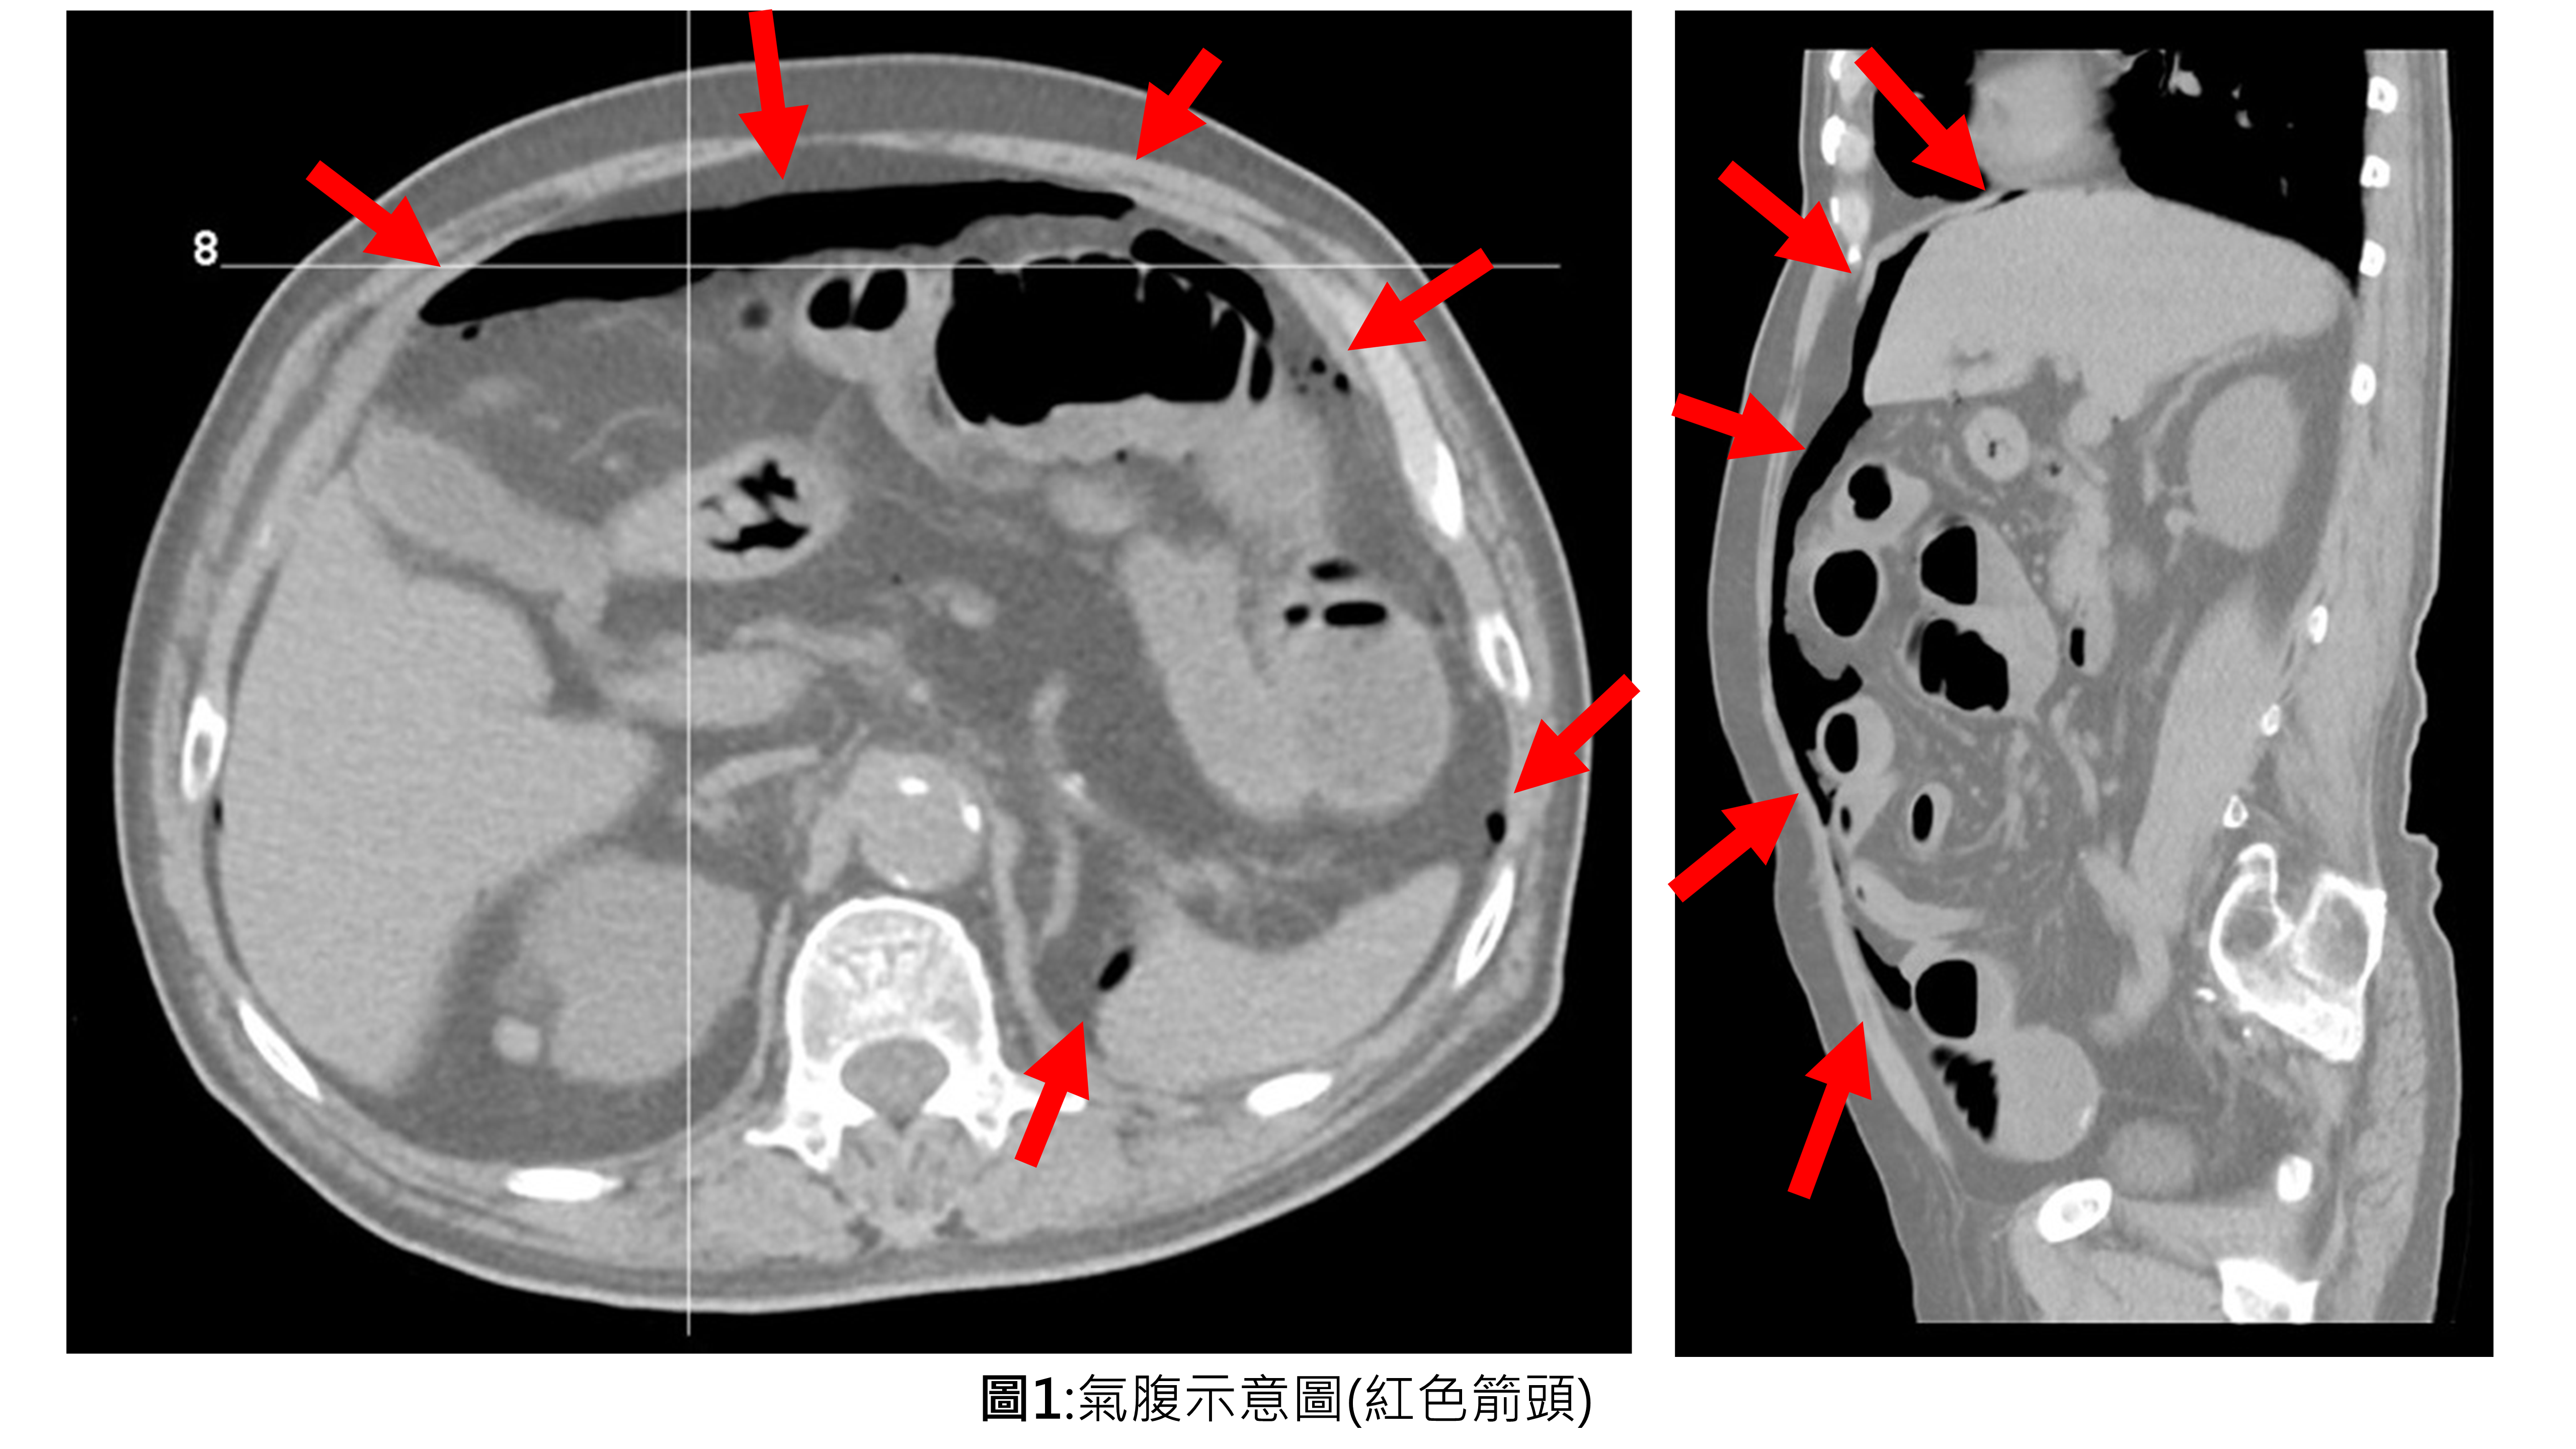

獲獎年度及獎項: 113國家發明創作獎 發明獎 金牌(專利行政企劃組)獲獎年度及獎項: 113國家發明創作獎 發明獎 金牌 專利證號: I801273 參展單位: 薛承君 展品名稱: 腹腔異常游離氣體深度學習檢測方法及腹腔異常游離氣體深度學習檢測系統 氣腹(Pneumoperitoneum)的定義為腹腔內有游離氣體(Free air)(圖1);腹痛病人若在影像學上產生氣腹,臨床上通常代表器官/腸子破裂,屬於高危險性,需緊急手術以挽救性命,延誤診斷將導致敗血性休克及多... - 5